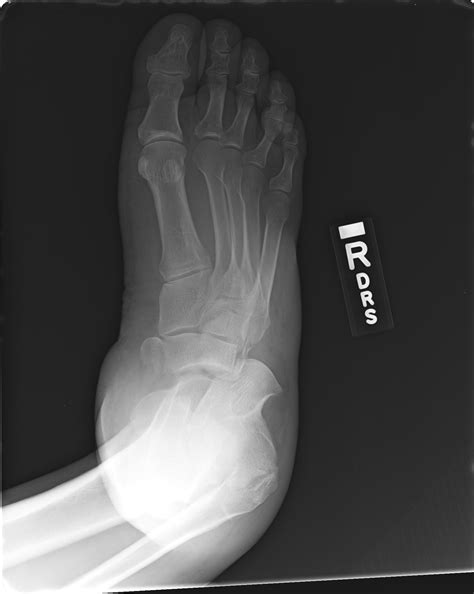

Stress Fracture. Marching Fracture Of The Foot. Fracture Of The

Pediatric Stress Fracture | Pediatric Radiology Reference Article

Stress Fracture Foot Symptoms: How to Spot and Treat Early